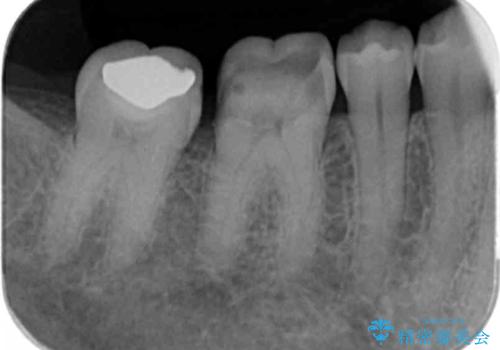

銀歯が取れた セラミックでのやり替え

- 右下奥歯の詰め物が取れたとのことで来院されました。

セラミックでの治療をご希望されましたが、残っている歯が少なかったためクラウンでの治療を行いました。

もう一つ奥の歯に関してもセラミックにやり替えたいとのことでしたので、こちらはインレーでの治療を行いました。

残る歯が薄かったり、十分な量を確保できない場合はクラウンで治療した方が今後の破折リスクを抑えることができます。